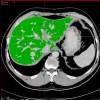

Automatisches Füllen der Leber

Klicken Sie einfach Punkte in der Leber an. Der 3D-Füllalgorithmus breitet sich von dort aus aus und füllt die Leber - ohne häufig auszulaufen.